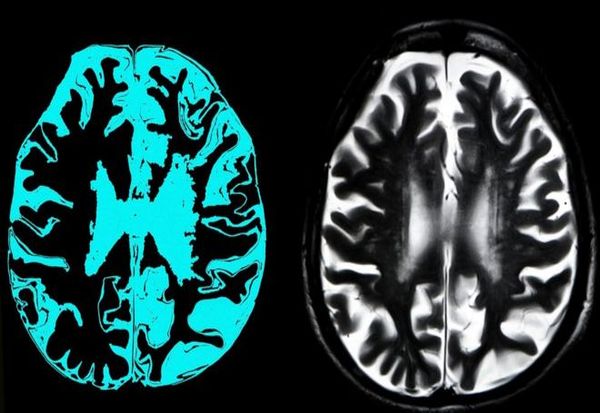

Фото: Getty Images

Целта на „адуканумаб“ е протеинот амилоид, кој формира огромни наслојки во мозокот на луѓето со Алцхајмерова болест. Научниците веруваат дека овие наслојки се токсични за мозочните клетки и дека нивното отстранување со помош на овој лек би претставувало голем чекор напред во третманот, иако не во целосното лекување на деменцијата.

Алцхајмеровата болест е прогресивна болест на мозокот што се карактеризира со губење на меморијата и расудувањето и промени во личноста. Покрај тоа што е водечки здравствен проблем, ова нарушување е најчестата форма на деменција, која бара навремено препознавање и лекување.